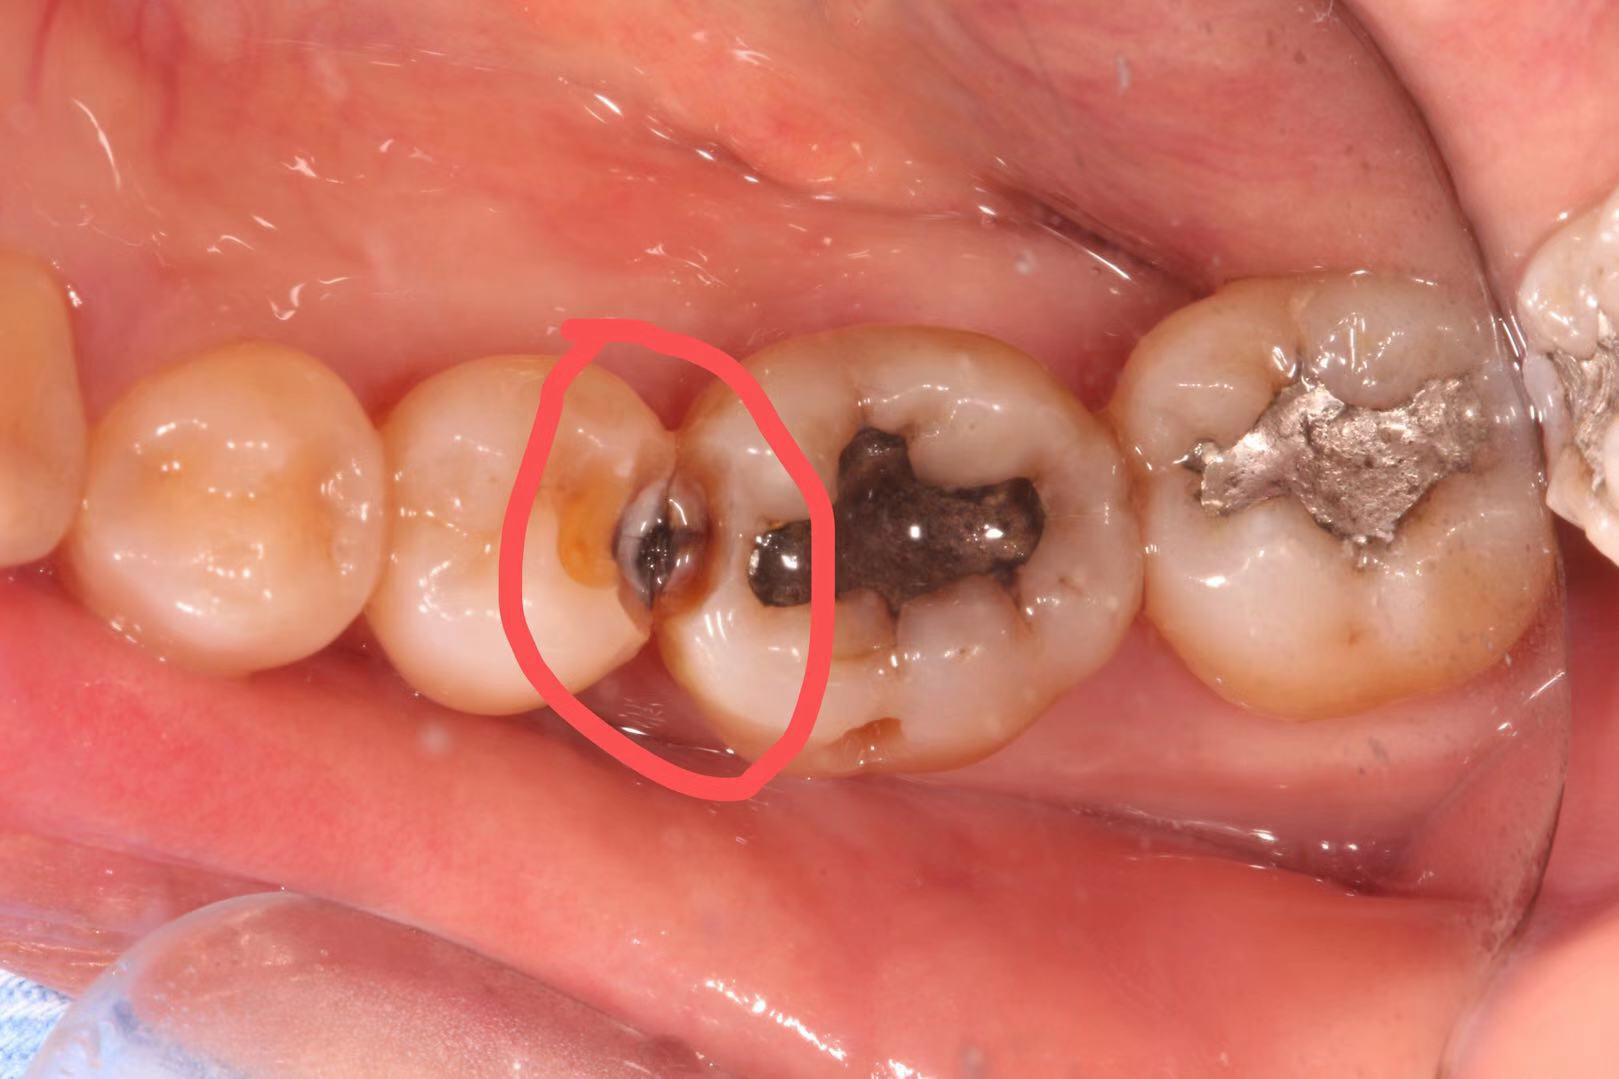

患者多年前银汞充填,因边缘微渗漏导致继发龋坏,我院采用相较于传统补牙更耐用、美观、可承受更大咬合力的修复方式:嵌体修复。

治疗步骤:1 去净龋坏, 2 制备洞形,3 扫描,4 切割制作,5 戴牙。